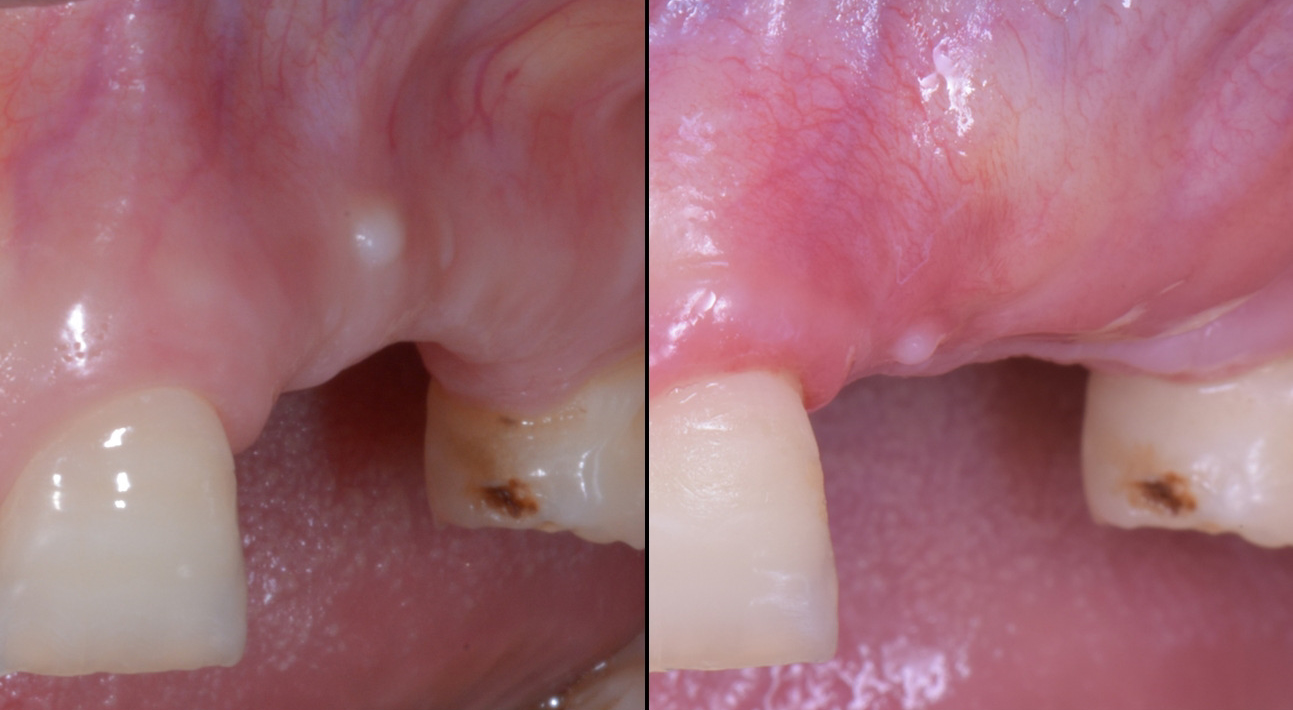

Fornice completamente accorciato con inserzioni muscolari palatali rispetto al centro della cresta a 8 mesi dalla prima chirurgia.